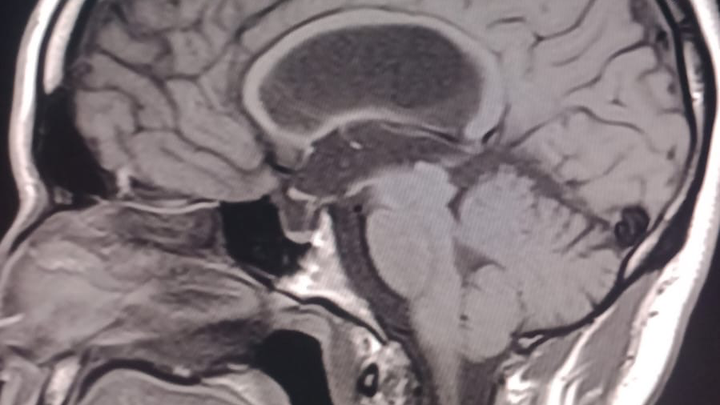

Our dear Cesar Eduardo Rodríguez Ortiz has been fighting seizures since he was just two years old, after suffering a head injury as a baby. Despite years of struggle, his strength and spirit have never faded.

On October 17, 2025, Cesar underwent a major brain surgery to help control his severe epilepsy. By God’s grace, the surgery went well, and he is now beginning his road to recovery.